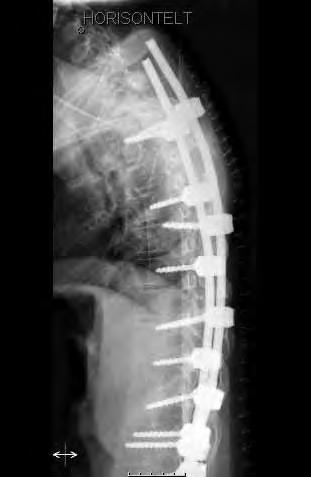

12 årig flicka med CP. Hon hade fått en starkt försämrad sittställning på grund av progressiv lumbal skolios. vid opererationen användes bakre teknik för att först få korrektion av den lumbala skoliosen. Operationen extenderades ovan Th12 med tunnare stag som är längre än nödvändigt vid operationstillfället. Syftet var att man med denna konstruktion (Shilla-teknik) har stag som ska kunna glida i skruvhuvudena i bröstryggen, allt för att kunna få thorax att växa ytterligare. I thorakalryggen infördes skruvarna transmuskulärt med hjälp av navigationsutrustning för att inte stimulera till bakre fusion.

Lateral bild av övre delen av konstruktionen där de ”för långa” stagen syns väl.